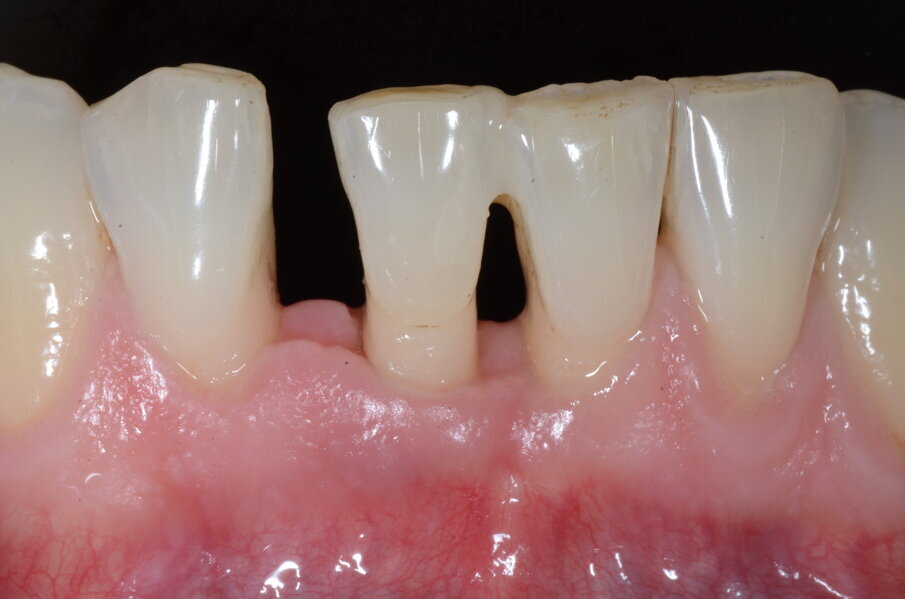

Fig. 6d - Lembo sollevato con preservazione papille.

Fig. 6e - Difetto infraosseo mesiale.

Il Paziente veniva premedicato con Zitromax 500 mg e Ibuprofene 400 mg. Eseguita anestesia loco regionale con articaina 1:100.000 con adrenalina veniva sollevato un lembo muco periosteo a spessore totale con tecnica di preservazione di papilla MPPT (Cortellin i 1995) e incisione intrasulculare (Figg 6d, 6e). Il difetto in sede interprossimale e vestibolare è stato degranulato con ultrasuoni e curette manuale. Raggiunta la perfetta decontaminazione del sito è stata preparata la barriera GUIDOR matrix barrier partendo dalla configurazione specifica per difetti interprossimali (DC double curved) in modo da renderne corretta la dimensione mesio distale e apico coronale (Fig. 6f) .

Il Paziente è stato intercettato in visita con diagnosi di parodontite cronica generalizzata da moderata a severa a seconda dei siti. È stata eseguita la terapia non chirurgica in regime di Full mouth disinfection in unica seduta seguita da controlli settimanali fino al raggiungimento della guarigione a 2 mesi dalla strumentazione. In tale fase sulla base della valutazione dei siti con PD>5 mm e dell’anatomia dei difetti infra-ossei o sovra ossei presenti viene normalmente discussa con il paziente la fase di chirurgia correttiva, se necessaria. Nel Paziente in questo caso residuava a livello di 41 un difetto infra-osseo (Figg. 6a-6c).